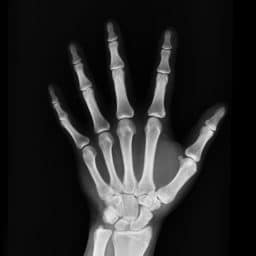

Sound waves entering the ear are funneled to the eardrum, a thin membrane attached to the ossicles – a trio of tiny (and extremely fragile) bones in the middle ear.

Because osteoporosis weakens bones, the ossicles are even more vulnerable to fracture in patients with the bone density disease.

Damage to the ossicles results in hearing loss.